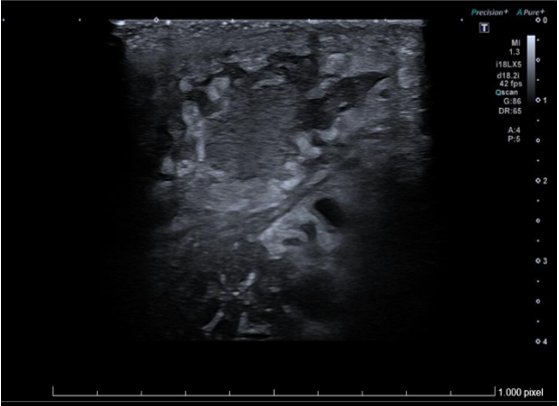

Ecografía de partes blandas de axila izquierda: Piel engrosada con aspecto hipoecogénico y heterogéneo. Tejido celular subcutáneo con cambios inflamatorios y edema, que simula imagen en forma de nubes. Colección de 13x36 mm en tejido celular subcutáneo con márgenes irregulares, contenido ecogénico fluctuante con trazos hiperecogénicos periféricos. Vasos regionales permeables sin signos de trombosis. Hallazgos compatibles con absceso subcutáneo y celulitis.

La ecografía es una herramienta efectiva y accesible desde atención primaria para el diagnóstico de patología de partes blandas ya que permite hacer un diagnóstico diferencial entre abscesos, adenopatías, hidradenitis supurativa y quistes, entre otros.